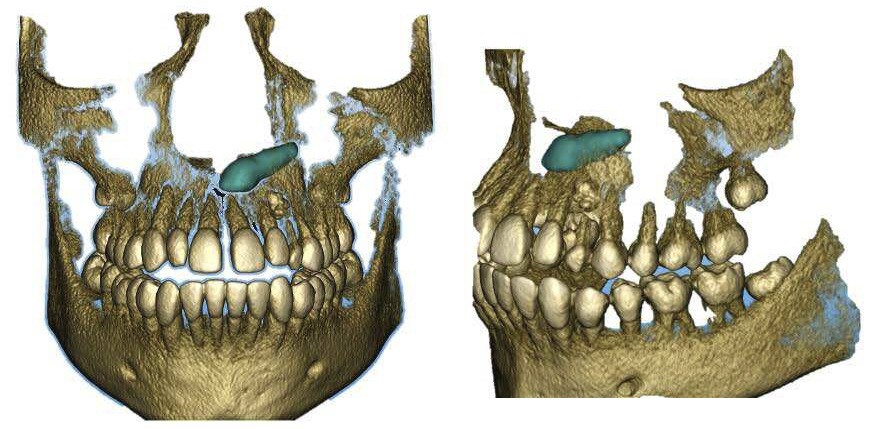

La radiographie panoramique permet de confirmer l’inclusion de la 23, apicale aux dents 21 et 22, ainsi que la présence d’un odontome en apical de la 63. Ces éléments nécessitent la réalisation d’un CBCT.

Le CBCT révèle une position très apicale de la 23. L’apex est fermé.

- mise en place de la 23 sur l’arcade par auto-transplantation étant donné la position très défavorable de la dent, associée à l’extraction de la 63 et de l’odontome ;

Auto-transplantation

Une fois l’espace nécessaire obtenu, des cales molaires sont réalisées pour limiter les interférences occlusales avec la 23. La 63 et l’odontome sont extraits (fig. 4). Un lambeau est levé et la réplique 3D de la 23 est essayée dans l’alvéole, qui est adaptée en fonction (fig. 5). La 23 est prélevée de façon atraumatique (fig. 6) et auto-transplantée (fig. 7). Après suture du lambeau (fig. 8), une contention par arc acier 0,019×0,025’’ avec un CVI entre la dent et l’arc orthodontique est réalisée (fig. 9). Trois ou quatre semaines après l’auto-transplantation (fig. 10), le traitement endodontique est effectué (fig. 11). Un bracket orthodontique pourra être collé de façon passive, et la dent prise en charge avec un arc Niti 0,017 x 0,025’’ (fig. 12).